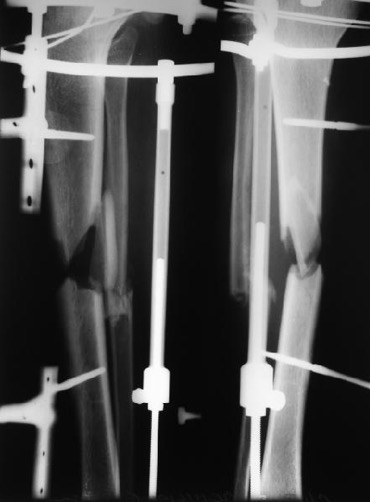

Операцию сделали, инфекции не выявлено, резецированы концы бедренной кости на 10 - 20 мм с каждой стороны, дистальный конец был нежизнеспособен, щели перелома выполнены губчатым аутотрансплантантом, также по передней поверхности фиксирован винтами губчато-кортикальный аутотрансплантант.

Клинически укорочение 3,5 - 4 см. Больная была предупреждена о возможной резекции. Возможна компенсация этого укорочения неоперативными методами.

Уважаемые коллеги! У нас возникла дискуссия относительно сроков осевой нагрузки в обсуждаемом случае. Если бы перелом обычный поперечный дали бы нагрузку через 1 неделю. Здесь же в результате резекции - поперечный "перелом" , но не с плотным контактом, щель перелома утрамбована губчатой аутокостью. Что произойдет с аутотрансплантантами в случае ранней осевой нагрузки ?

Величина резекции – это компромисс между желанием сделать её в пределах жизнеспособных тканей и возможными проблемами, связанными с укорочением. Выбор метода фиксации влияет на особенность техники резекции. При интрамедуллярном остеосинтезе, конечно же, нужна максимальная конгруэнтность (параллельность) контактирующих поверхностей. В идеале поперечный срез, в крайнем случае – немного косой. В данном случае большей пользой было бы немного укоротить проксимальный фрагмент, добившись строго поперечной резекции, чем использовать трансплантат. При фиксации аппаратом больше свободы для маневра, так как можно обеспечить плотный контакт даже в тех случаях, когда опилы костей не совсем параллельны. Пусть лучше срастется с угловым смещением, чем не срастется вообще. Резекция в подобных случаях при кажущейся незамысловатости, не является простой. При многолетнем анамнезе, десятках операций в этой зоне, пробираться приходится через сплошной рубец.

1. Операцию делали следующим образом: выполнена поперечная (на глаз) резекция дистального отломка до жизнеспособных (кровяная роса на опиле), но не "полумертвых" тканей, затем минимальная резекция проксимального отломка также поперечная (на глаз). После введения стержня и спирального винта увидели, что идеального сопоставления не получилось. Подскажите, как технически надо было добиться строго поперечной резекции -подпиливать кость на уже установленном стержне по медиальной и задней поверхностях, либо удалять, подпиливать кость и вновь устанавливать систему PFNa?

5. Решили пойти путем ранней нагрузки (ходьба с тростью с нагрузкой до 50% веса тела). 2 винта в дистальном метафизе создают возможность самостоятельной динамизации. Выложим снимки через 6 недель.